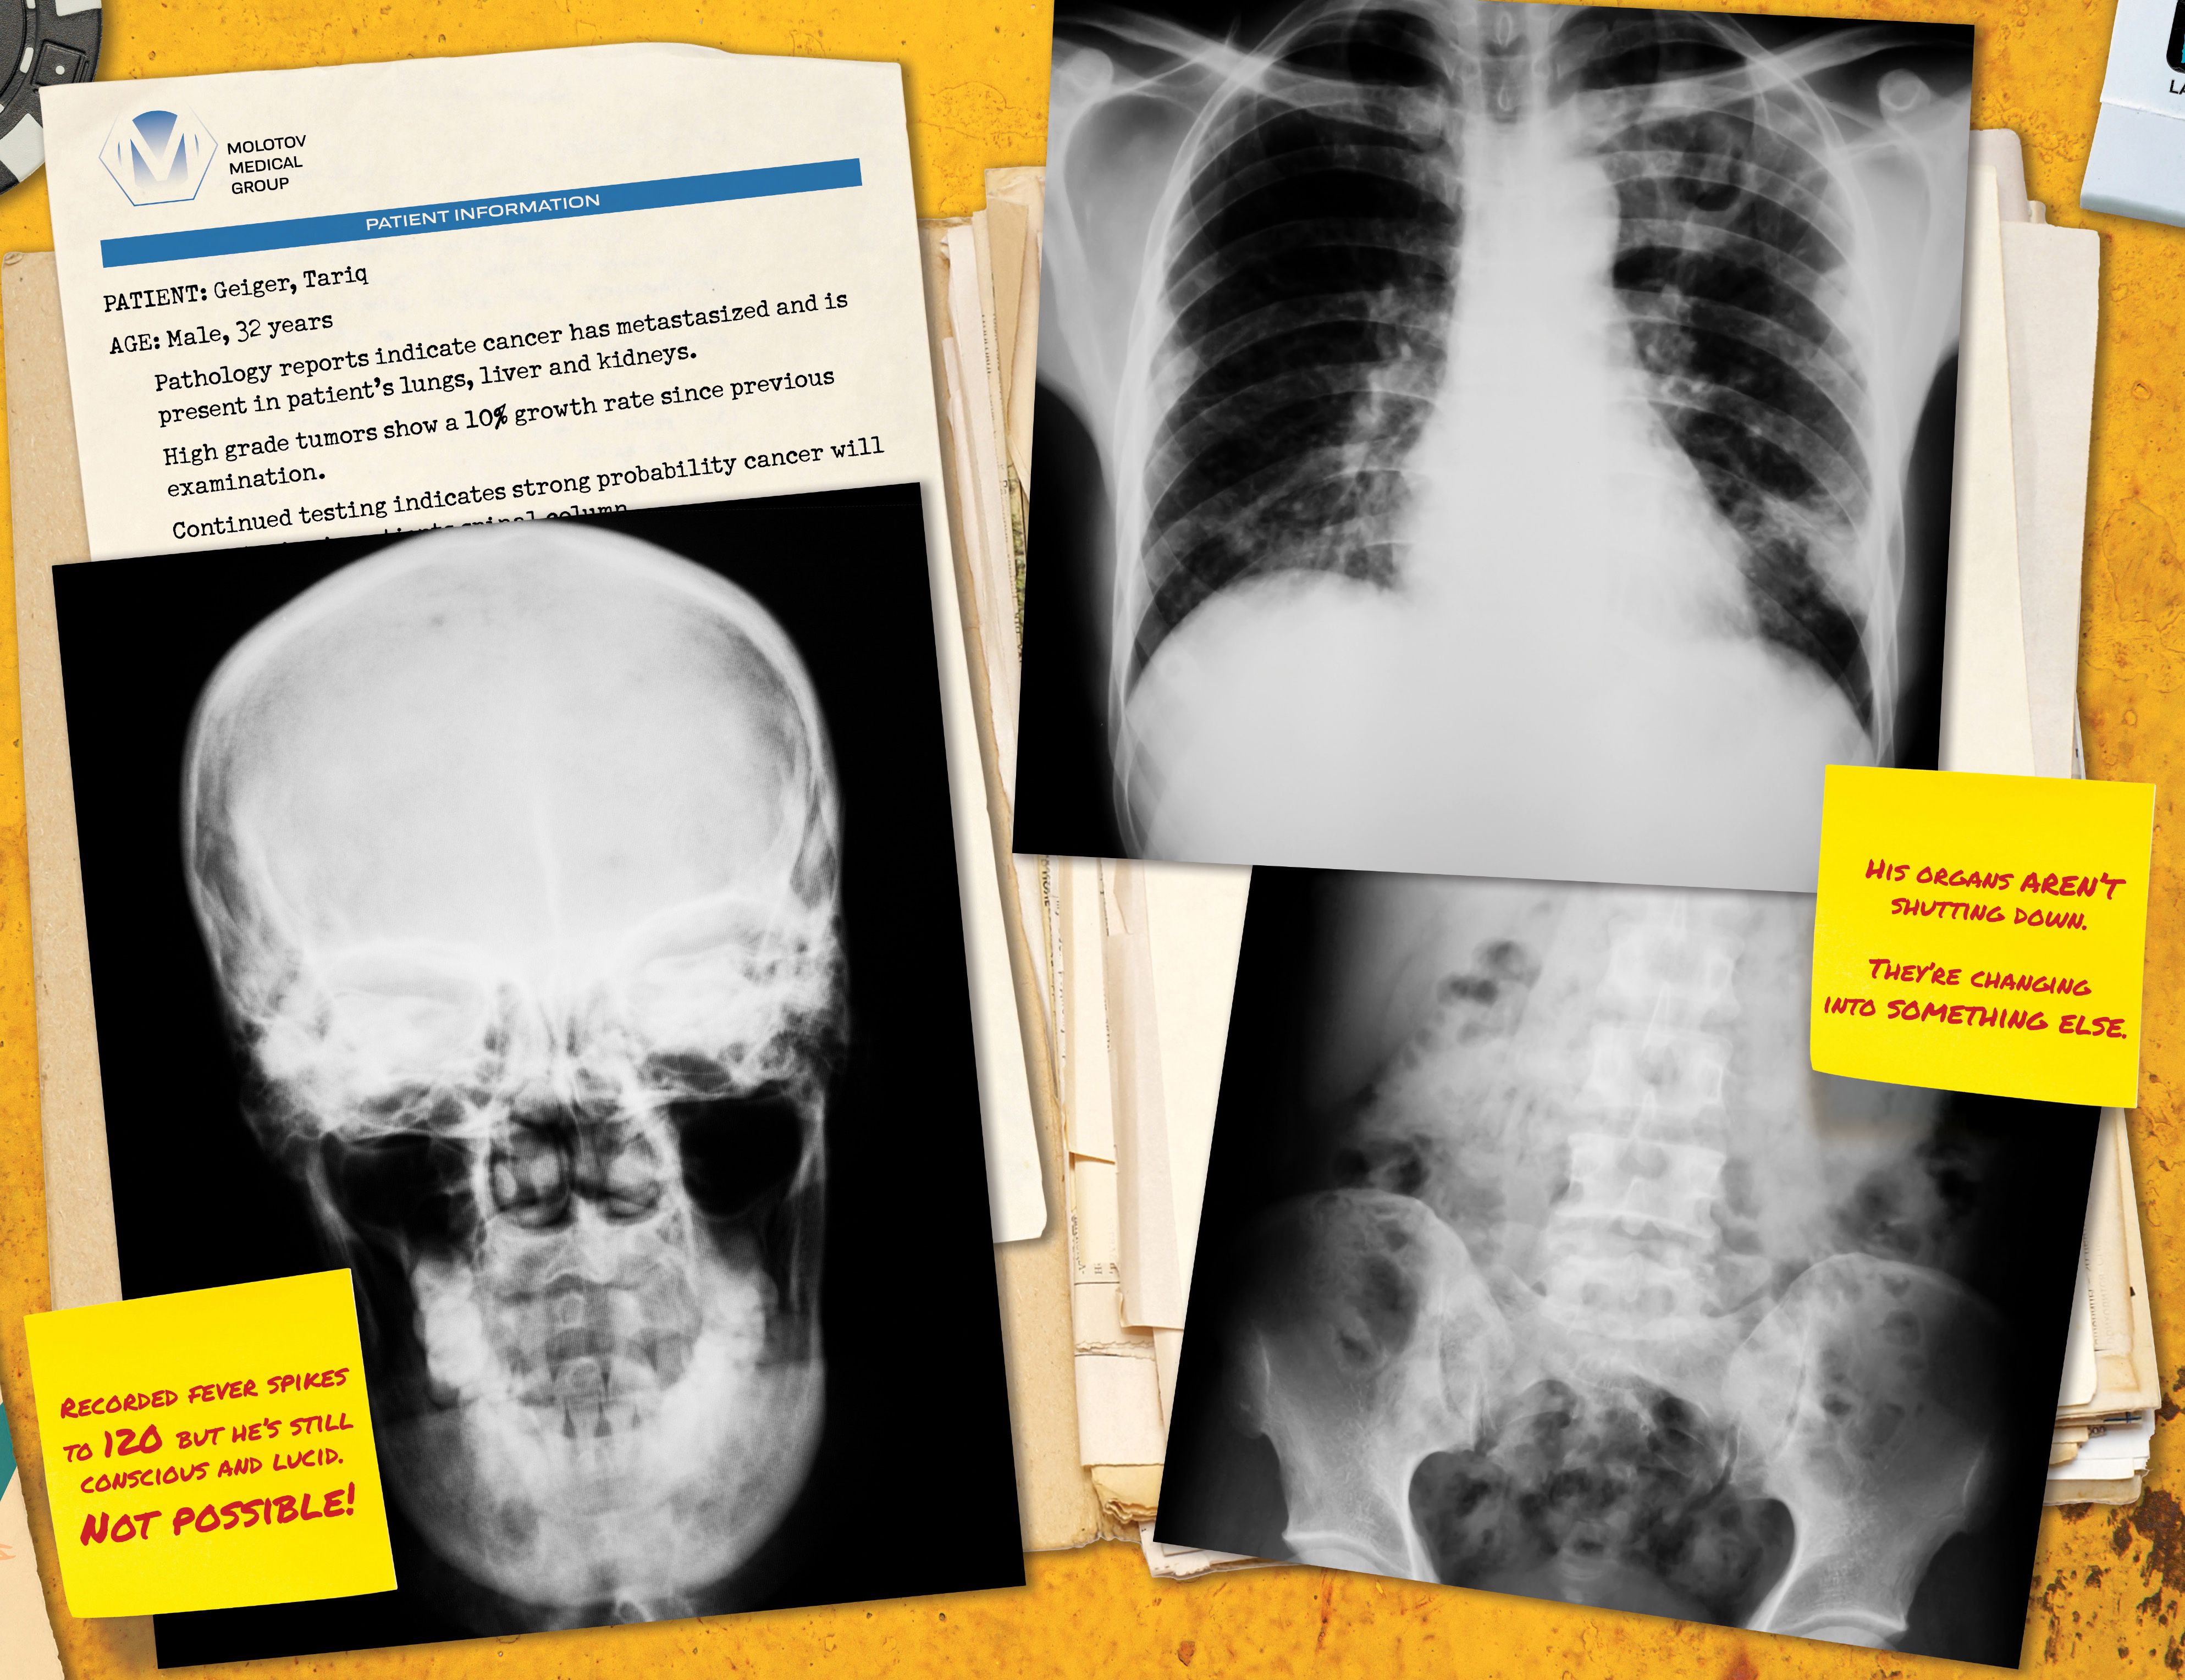

File: Geiger_v01-004.jpg (646 KB, 1987x3056)